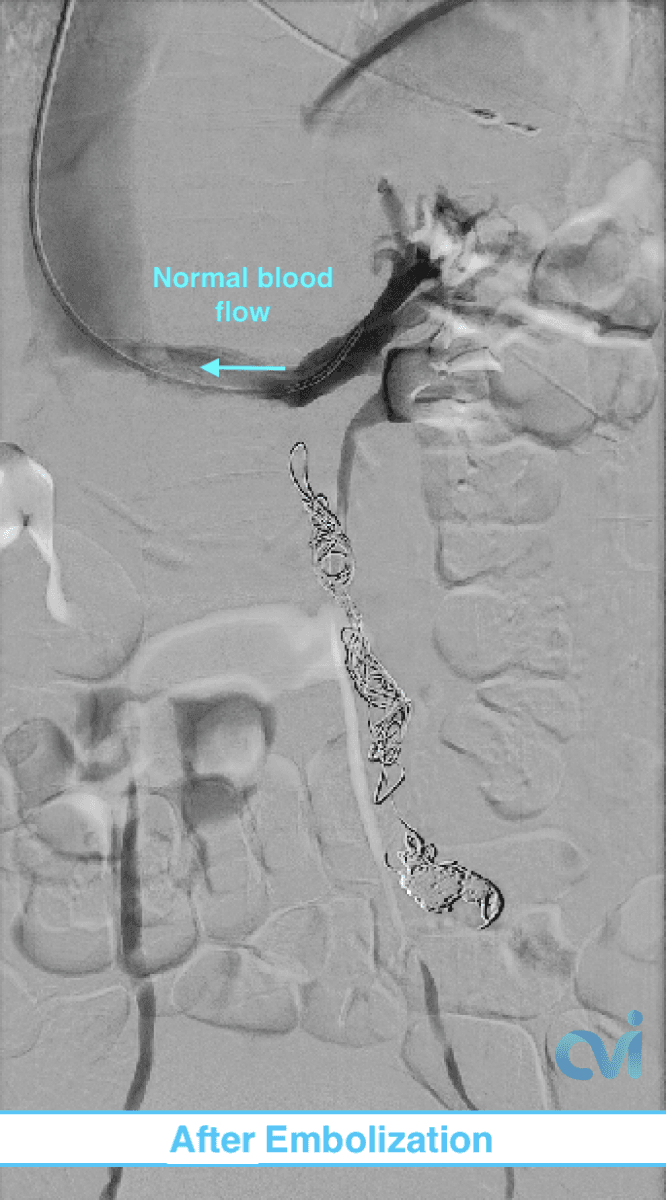

Embolization – The gold standard for treatment is closure of the abnormal veins, similar to varicose veins in the legs. This is called “Ovarian vein embolization.” This is an outpatient procedure that requires no sedation or general anesthesia. Read below for further details.

What is Ovarian Vein Embolization?

Ovarian vein embolization is a non-surgical outpatient procedure that is performed through a tiny nick in the skin under moderate sedation.

During this procedure, our image-guided specialist will numb the skin and insert a catheter (a tiny tube) into a vein in the neck or groin. The placement is done with precision using ultrasound guidance minimizing pain.

Using x-ray guidance a smaller catheter is then guided into the abnormal ovarian or pelvic veins. The abnormal vein is then treated by placing tiny coils and a specialized fluid causing the vein to seal down. This then restores normal blood flow in the body and improves related symptoms.

There are no stitches, major incisions, hospital stay requirements, or significant downtime. Patient’s go home with a Band-Aid.